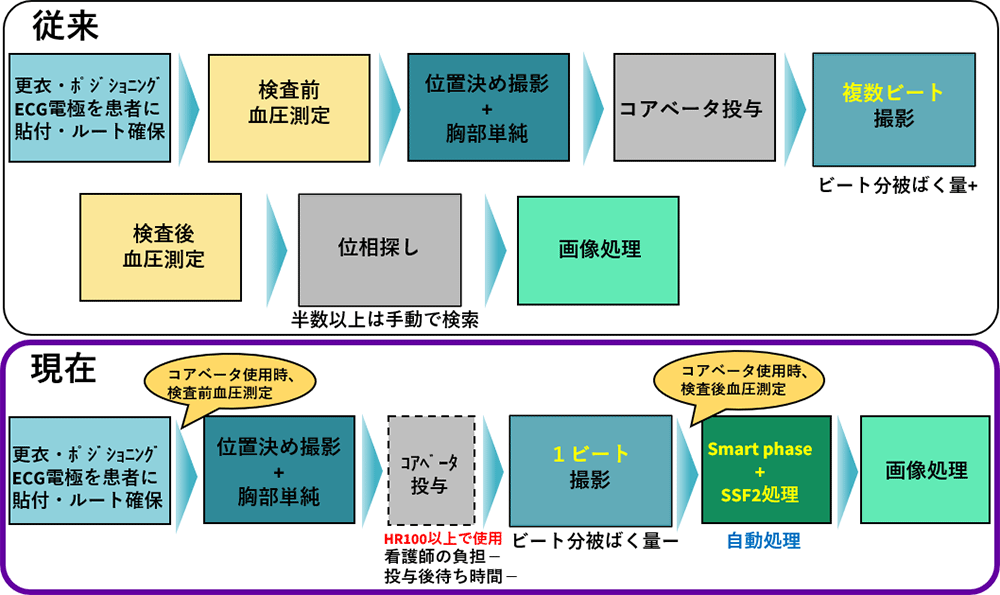

Revolution CTによる心臓CT・Dual Energy・高速撮影の臨床的メリット